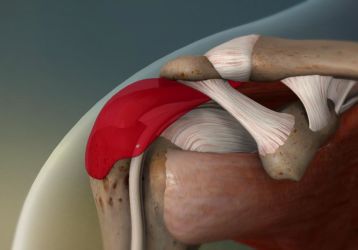

Симптомы, диагностика и лечение субакромиального бурсита плечевого сустава

Причины и провоцирующие факторы субакромиального бурсита плечевого сустава, диагностика, методы консервативного и хирургического лечения болезни.